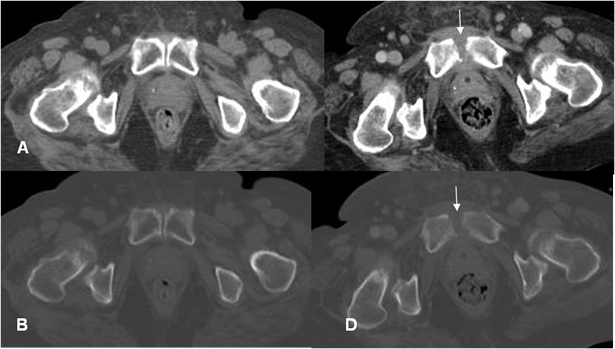

Fig 31 B. Evolución de osteomielitis.

A: TAC axial en ventana de tejido y B: en ventana ósea. Sínfisis púbica de aspecto normal.

B: TAC axial en ventana de tejido y D: en ventana ósea. Erosión en las corticales del pubis, con cambios inflamatorios en los tejidos blandos, por osteomielitis.